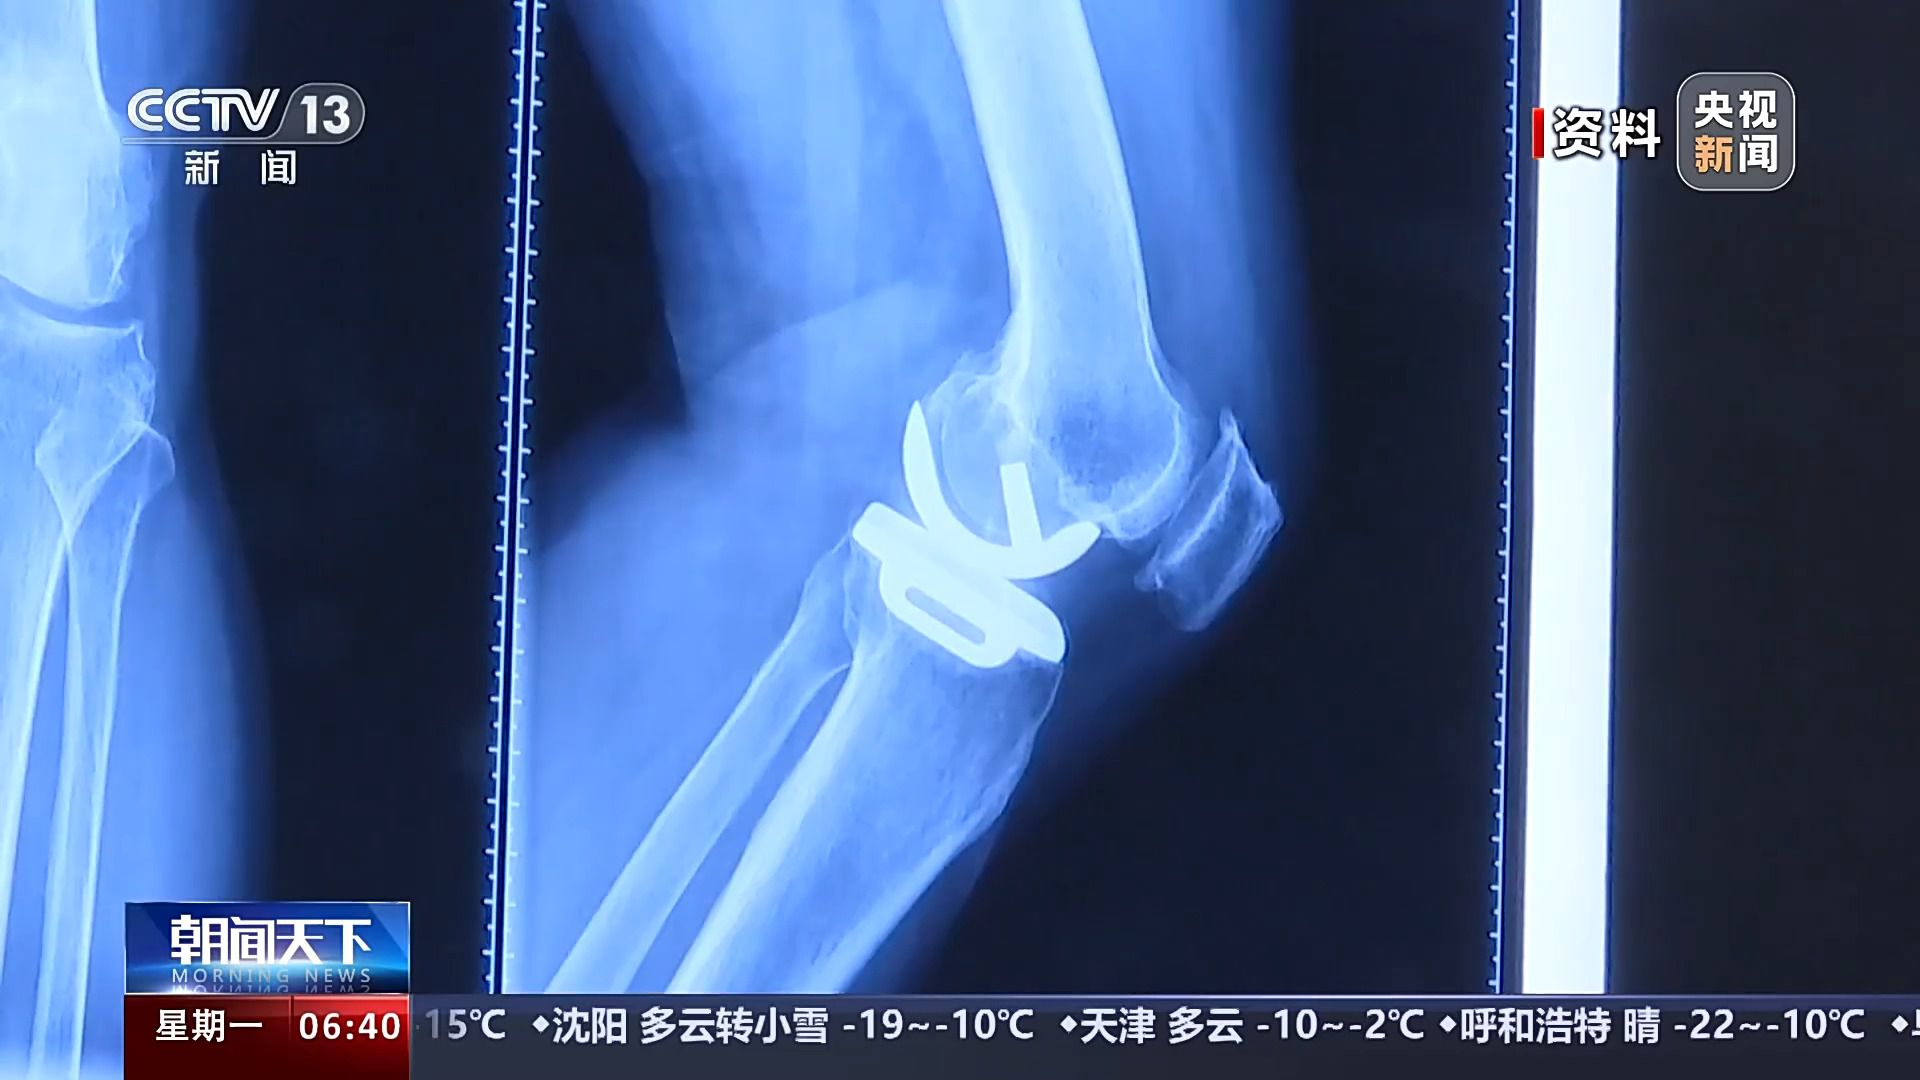

保膝手术主要包括截骨术和单髁置换术,其中截骨术在解决患者疼痛症状的同时,阻止下肢异常应力对膝关节的进一步损伤,膝关节内所有软骨韧带、半月板都得到了保留。内侧单髁置换术,使膝关节外侧健康的软骨和半月板得到了保留,膝关节内外侧的韧带维持原有状态,患者康复后,拥有正常的膝关节功能。